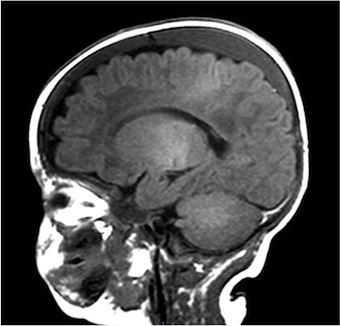

Per un miglior inquadramento clinico è stata pertanto posta indicazione all’esecuzione di RM encefalo. L’esame ha mostrato falde sottodurali intorno agli emisferi cerebrali di natura subacuta o cronica, emorragie in sede subaracnoidea e una sottile componente emorragica in fossa cranica posteriore dietro del cervelletto (Figura 1).

Nel sospetto di shaken baby syndrome è stata richiesta la visita oculistica con fundus oculi, che ha rilevato numerose emorragie diffuse su tutto l’ambito retinico, bilaterali e la skeletal survey che è risultata negativa. A necessario completamento diagnostico è stato indagato il profilo della coagulazione e sono stati eseguiti esami metabolici per escludere alcune patologie come la glutarico aciduria e la sindrome di Menkes, che possono essere responsabili di quadri clinici simili a quello descritto, e che sono ancora in corso.

Il sospetto di SBS non deve essere dimenticato quando ci troviamo di fronte a un neonato o un piccolo lattante con segni neurologici senza cause apparenti e che presenti i fattori di rischio. Ruolo fondamentale per la diagnosi è rappresentato dalle neuroimmagini, in particolare la RM encefalo e rachide che, oltre a mostrare le lesioni caratteristiche (ematomi subdurali, le emorragie subaracnoidee, lesioni ipossico-ischemiche), può rilevare a livello cervicale altri segni tipici del trauma cervicale della SBS (ematomi spinali, edema dei tessuti molli e dei legamenti cervicali, lesioni alle vertebre cervicali). La SBS ha una prognosi severa: infatti circa il 25-30% dei pazienti muore, mentre il 60-70% mostra spesso esiti.